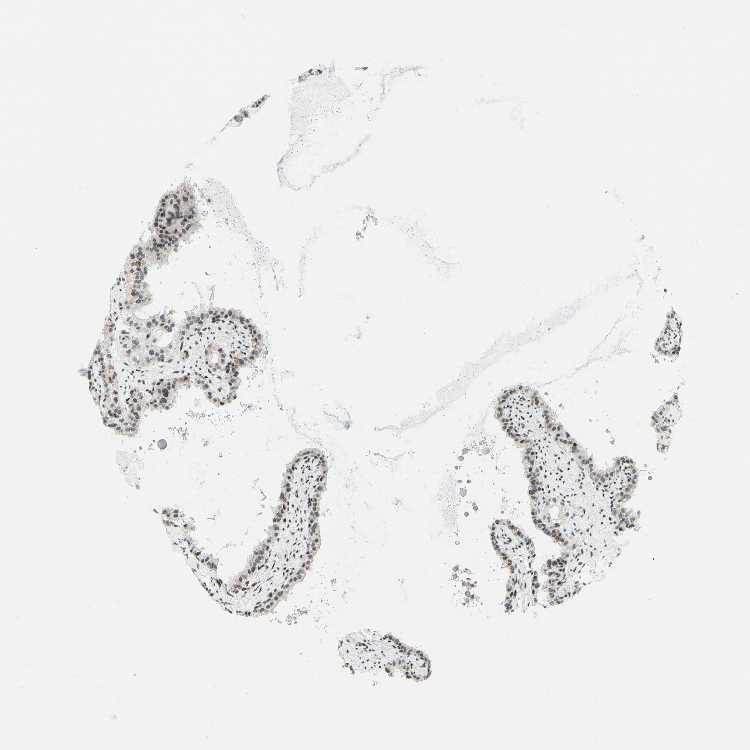

SEMINAL VESICLE - Antibody stainingi

Antibody staining in the annotated cell types in the current human tissue is reported as not detected, low, medium, or high, based on conventional immunohistochemistry profiling in selected tissues. This score is based on the combination of the staining intensity and fraction of stained cells.

Each image is clickable and will lead to virtual microscopy that enables deeper exploration of all samples and also displays staining intensity scores, fraction scores and subcellular localization as well as patient and tissue information for each sample.

Antibody HPA048677Antibody HPA056480Antibody CAB011574

Glandular cells LowNot detectedMedium